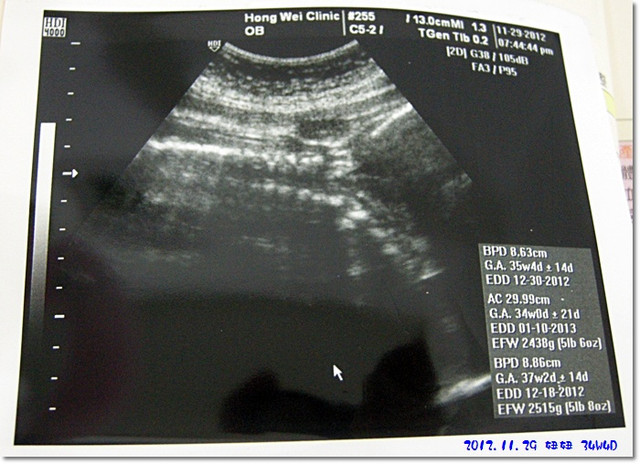

這次檢查時妞妞不是很配合,都是趴著滴...

所以最後出來的超音波相片只有看到妞妞的背部的脊椎骨![]()

目前初估妞妞的體重為2500g

比兩個禮拜前產檢時的體重多了100公克而已![]()

陶醫師是說很ok,在標準直內就好

34週邁向35週囉